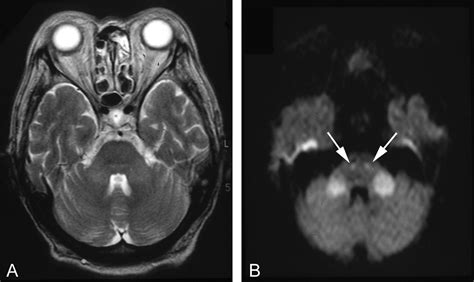

• Magnetic Resonance Imaging (MRI): MRI provides detailed images of the brain, allowing for the visualization of structural abnormalities, such as tumors, strokes, or traumatic injuries. Functional MRI (fMRI) can also be used to assess brain activity and connectivity.

• Neuroimaging: Advanced imaging techniques, such as diffusion tensor imaging (DTI) and functional MRI, are being used to study the connectivity and functional organization of the cerebral peduncles brain. These techniques provide insights into the structural and functional changes associated with neurological disorders.

• Case Study 1: Stroke: A 65-year-old patient presents with sudden onset of weakness on the right side of the body and difficulty speaking. An MRI reveals an ischemic stroke in the left cerebral peduncles brain. The patient undergoes thrombolytic therapy to dissolve the clot and is referred to a rehabilitation program for physical and speech therapy. Over time, the patient shows significant improvement in motor and language functions.

• cerebral peduncle mri anatomy